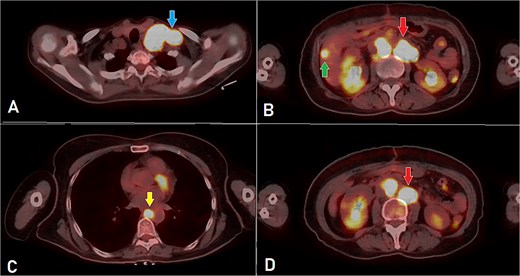

A computed tomography (CT) scan was performed, and the patient underwent a right hemicolectomy using a laparoscopic-assisted approach, with en bloc resection of the tumor and lymphadenectomy. The procedure was uneventful, with no intraoperative complications, and the patient had an unremarkable immediate postoperative recovery. The staging was determined as T4bN2bMx. Further imaging revealed enlarged mediastinal, supraclavicular, and retroperitoneal lymph nodes, with a solitary liver lesion (Fig. 1). A biopsy from the supraclavicular node indicated moderately differentiated adenocarcinoma of gastrointestinal origin. Molecular profiling showed wild-type RAS, intact MSI, mutant BRAF, and HER2 negative. The patient was started on capecitabine-oxaliplatin (CapeOX) with bevacizumab and completed 11 cycles with a marked clinical and radiological response (Fig. 2).

PET-CT scan (A) showing matted intensely hyper-metabolic left supraclavicular lymph nodes (arrow); (B) demonstrating intensely hyper-metabolic retroperitoneal lymph nodes (inferiorly pointing arrow) and a hyper-metabolic solitary hepatic lesion (superiorly pointing arrow); (C) demonstrating an intensely hyper metabolic mediastinal (para- oesophageal – station VIII) lymph node (arrow); and (D) revealing a few intensely hyper-metabolic retroperitoneal lymph nodes (arrow).